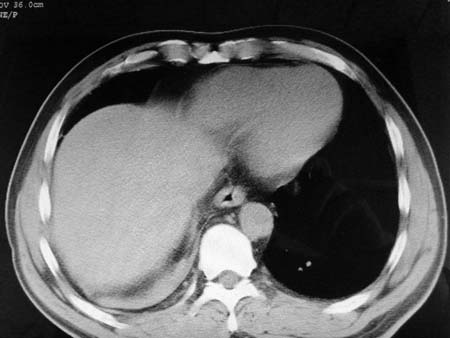

以下是引用qian在2008-4-27 17:02:00的发言:[br]考虑右下肺肺段隔离症伴有感染,建议做增强看看。

以下是引用zsl6918在2008-4-27 17:13:00的发言:[br]考虑右肺下叶炎性病变可能性大,建议抗炎治疗后复查,现有资料不能完全除外肺癌可能。